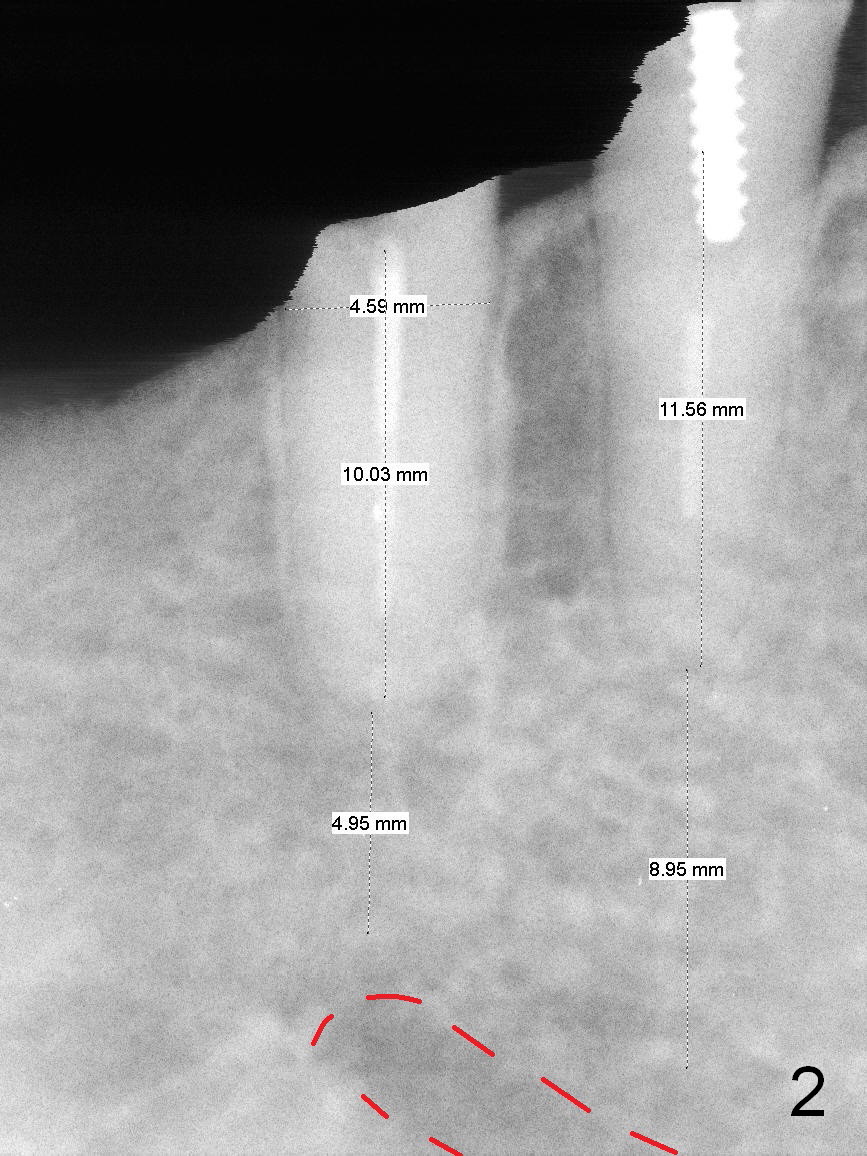

After restoring the implant at the site of #20, the patient returns for #28,29 implant placement (Fig.1,2). Bone level and distance from the Mental Loop (Fig.2 red dashed line) are different. It appears that longer implant can be placed at #28 than that at #29. Parallel pins are placed after initial osteotomy (Fig.3), it appears that the osteotomy at #29 should be moved mesially (arrow). Next PA shows that the position of the osteotomy at #29 is corrected (Fig.4). The position of the implants (4.5x17, 4.5x14 mm) appears ideal (Fig.5). After preparation for an immediate provisional, bone graft is placed in the remaining socket space (Fig.6 *). The splinted provisional is temporarily placed (Fig.7 P). The implant at #29 seems to be buccally placed. After CBCT confirmation, it should be removed for replacement. In addition to moving the osteotomy lingually, there is apparent space (~3 mm) to extend the osteotomy apcially for primary stability (Fig.8 arrow). The apical diameter of the implant is 3 mm.